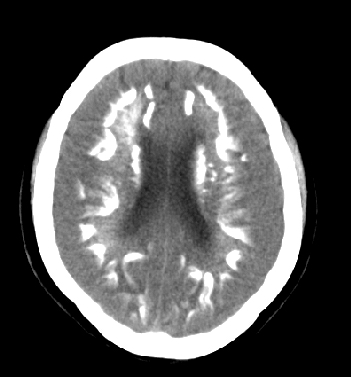

女性 38岁 病人脚弓反张 8岁以后不能行走 今年查pth11.9ng/ml(正常28ng/ml)

谢分享----甲状旁腺功能减退

这么弥漫的钙化还第一次见。

考虑甲状旁腺功能减退症,该病是因甲状旁腺激素分泌减少或功能障碍所引起的少见病。其特点是低血钙,高血磷,且血pth极低。因低钙常可引起神经精神激惹症状,包括手指,趾,口角麻木,严重时可出现肌肉痉挛,喉哮鸣和惊厥,甚至癫痫样发作,有的可出现抑郁症及精神失常。长期的高磷血症可引起脑内结构对称性多发性钙化,特别是小脑和基底节的钙化可致锥体外系症状,而钙化的ct表现为类似于脑出血的密度增高影。

原发性甲状旁腺功能减退症和fahr病都有神志上的改变等症状,且头颅ct检查均可见颅内出现钙化。但fahr病无pth低下,ct表现钙化影在大脑半卵圆中心皮髓质交界处、丘脑、小脑齿状核等处。 而甲状旁腺功能减退症pth极低,ct虽可见钙化影,但部位在小脑和基底节等处。